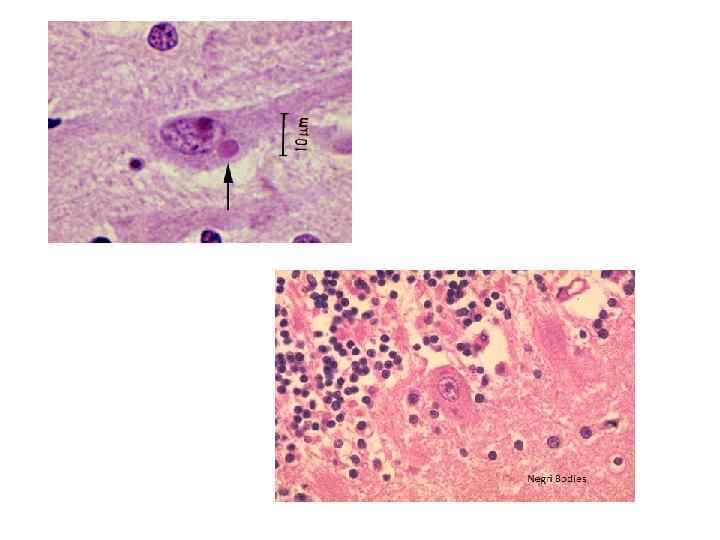

• Впервые клиническую картину бешенства описал Авл Корнелий Цельс (I век н. э. ), он же назвал это заболевание водобоязнью. До этого было известно, что заболевание возникало у людей после укусов животных. В 1885 г. Л. Пастер разработал антирабическую вакцину, полностью предохраняющую человека от развития заболевания. С 1906 г. в России начали функционировать пастеровские станции, где делали прививки против бешенства. В конце XIX - начале XX столетия В. Бабеш и А. Негри описали специфические эозинофильные включения в нейронах погибших от бешенства животных.

• Этиология • Возбудитель - РНК-геномный вирус рода Lissavirus семейства Rhabdoviridae. • Он имеет палочковидную или пулевидную форму, содержит два антигена: растворимый S-антиген, общий для всех лиссавирусов, и поверхностный V-антигенr, ответственный за развитие противовирусных иммунных реакций. • Вирус образует эозинофильные тельцавключения (тельца Негри, или Бабеша-Негри) в клетках аммонова рога, коры, мозжечка и продолговатого мозга.

• С изменениями в ЦНС связаны судорожные сокращения дыхательных и глотательных мышц, • повышение отделения слюны и пота, • дыхательные и сердечнососудистые расстройства. • В цитоплазме клеток мозга обнаруживают эозинофильные включения (тельца Бабеша-Негри). • В дальнейшем из ЦНС вирус попадает в различные органы и системы: скелетные мышцы, сердце, лёгкие, печень, почки, надпочечники. • Проникая в слюнные железы, он выделяется со слюной.